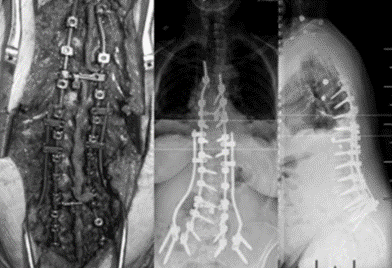

T10骨盆固定,出现交界性后凸

行翻修手术:T9/10SP截骨,延长到T4固定,预防性双侧肋骨固定(VEPTR)

图32-33 肋骨固定